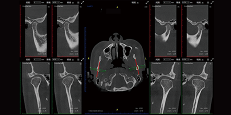

TMJ Diagnosis

SmartV-ENT has a visual pattern of comparison of left and right joints, allowing doctors to evaluate the diagnosis and treatment effect of temporomandibular joint diseases.